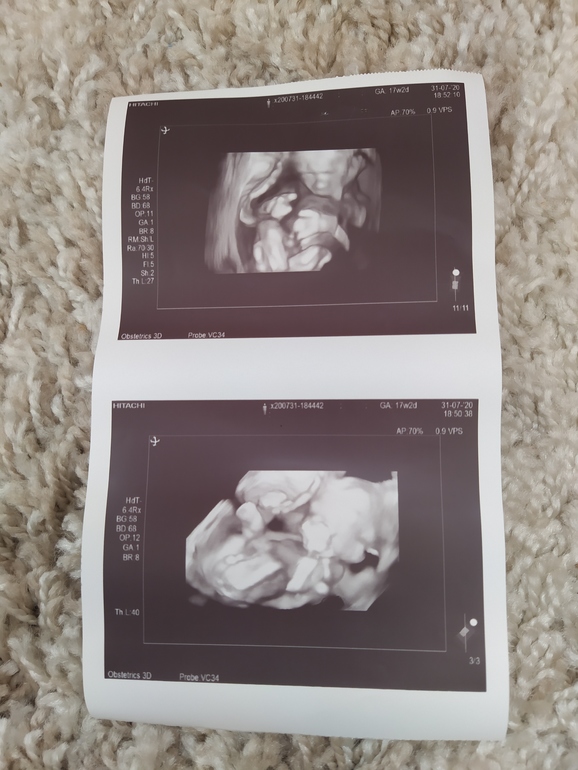

Внеплановый второй скрининг 17+2

До бесплатного скрининга ещё минимум две недели,решила сходить на платный,с сыночком все хорошо, никаких патологий нет,все на месте,но по фетометрии обгоняет поставили 18+3 снова крупненький видимо будет как и первый

Благодарю💗, ага вчера там ноги крестом сворачивал и руки,трудно его уловить было,врач сказала какой активный мальчик